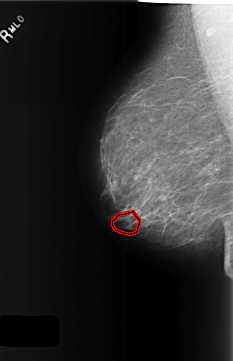

FILE: C_0369_1.RIGHT_MLO.OVERLAY

TOTAL_ABNORMALITIES 1

ABNORMALITY 1

LESION_TYPE MASS SHAPE LOBULATED MARGINS OBSCURED

ASSESSMENT 3

SUBTLETY 4

PATHOLOGY BENIGN

TOTAL_OUTLINES 1

BOUNDARY